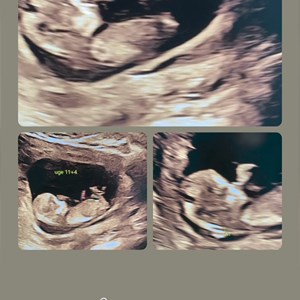

Tidlig scanning på foster uge 11+6 Når mor og far ser 1. gang hvor meget baby kan OG kan...